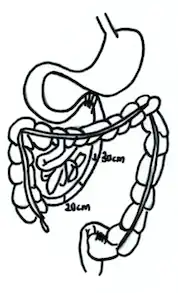

End-to-side jejunoileal bypass

This type of surgery was designed to overcome the shortcomings of jejunocolic bypass. First performed in 1969, it anastomoses the end of the proximal duodenum to the side of the distal ileum. However, owing to the possibility of reflux of ileal content to the blind loop, some surgeons doubted the effectiveness of this surgery.[5]

End-to-end jejunoileal bypass

This type of surgery appeared at the same time as end-to-side jejunoileal bypass. Some surgeons regarded this as a better option than end-to-side jejunoileal bypass because it prevented the reflux of ileal content to the blind loop. In order to achieve this, the end of the proximal duodenum is anastomosed to the distal ileum. The blind loop is drained to the transverse colon.[5] However, two studies revealed that both end-to-side and end-to-end jejunoileal bypass had similar weight loss effect.[5]